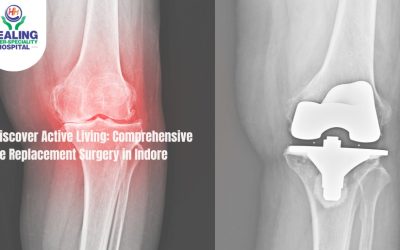

April 3, 2024 Orthopedic Rediscover Active Living: Comprehensive Knee Replacement Surgery in Indore Read more